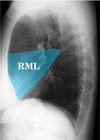

What is the smallest lobe of the right lung? What kind of shape does it look like in a lateral CXR?

* The right middle lobe is the smallest lobe * Triangular shape with narrowest end near the hilum

What is this CXR showing?

* RML pneumonia * You can rule out RLL pneumonia because there is no accumulation at the base of the lung. * A lateral CXR will have the best view for confirmation.